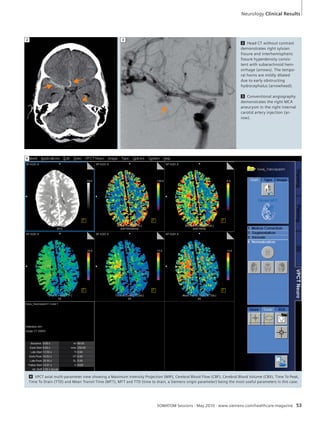

2 Winner in Neuro

(SOMATOM Definition AS / 7.55 mSv

dose), Robert McGregor, MD; Bound-ary

Trails Health Centre; Canada

History:

Carotid CTA and perfusion imaging

was obtained in a 55-year-old female

post SILK stent for right internal carot-id

aneurysm.

Diagnosis:

CTA revealed occlusion of the stented

right internal carotid artery. Perfusion

imaging demonstrated decreased

CBF, increased MTT, but maintained

CBV, indicating a large perfusion

defect without significant infarction.

Jury statement:

“The case nicely presents the potential

of comprehensive stroke assessment

by CT Perfusion. CT Perfusion may

suffer from image noise with unsharp

margins of the infarcted territory.

In this example, the margins of the

infarct are clearly displayed allowing

determination of the extent of the

infarction precisely.”